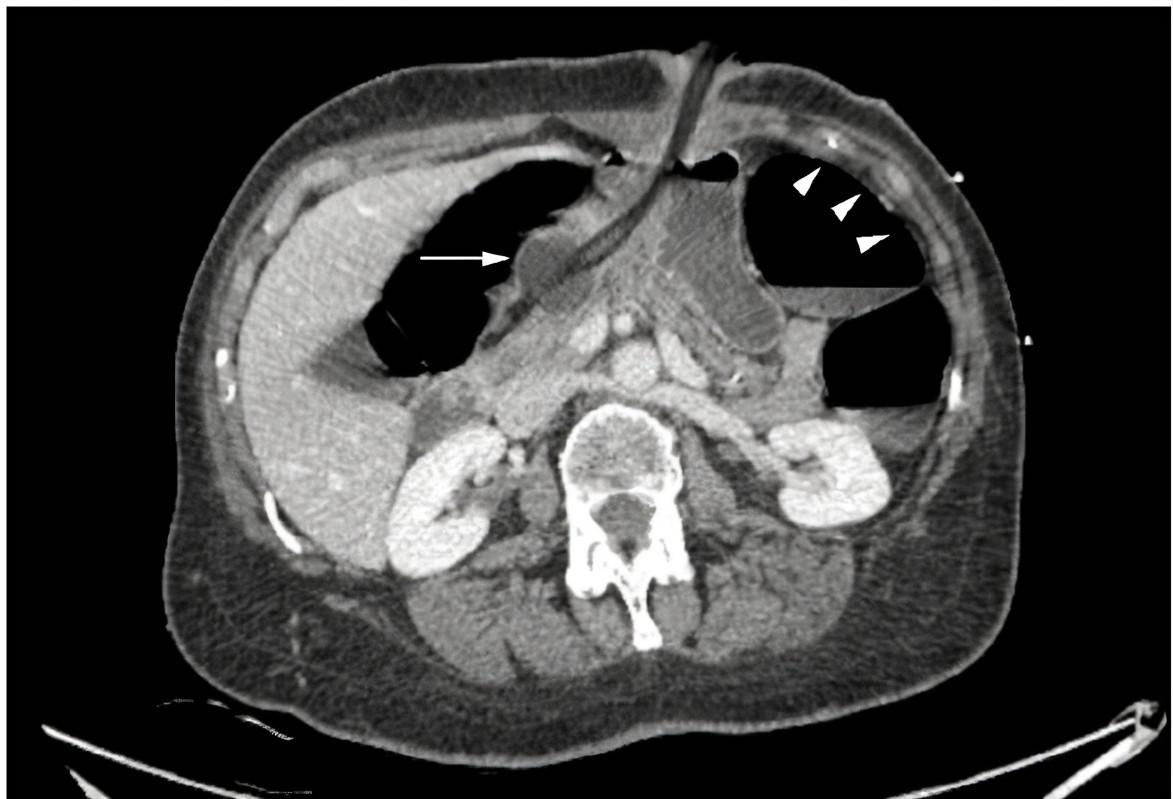

Elmoghrabi et al (2016) used a Foley to provide temporary hemorrhage control in a patient with a penetrating traumatic injury to the root of the aorta.

(Article is open access) ncbi.nlm.nih.gov